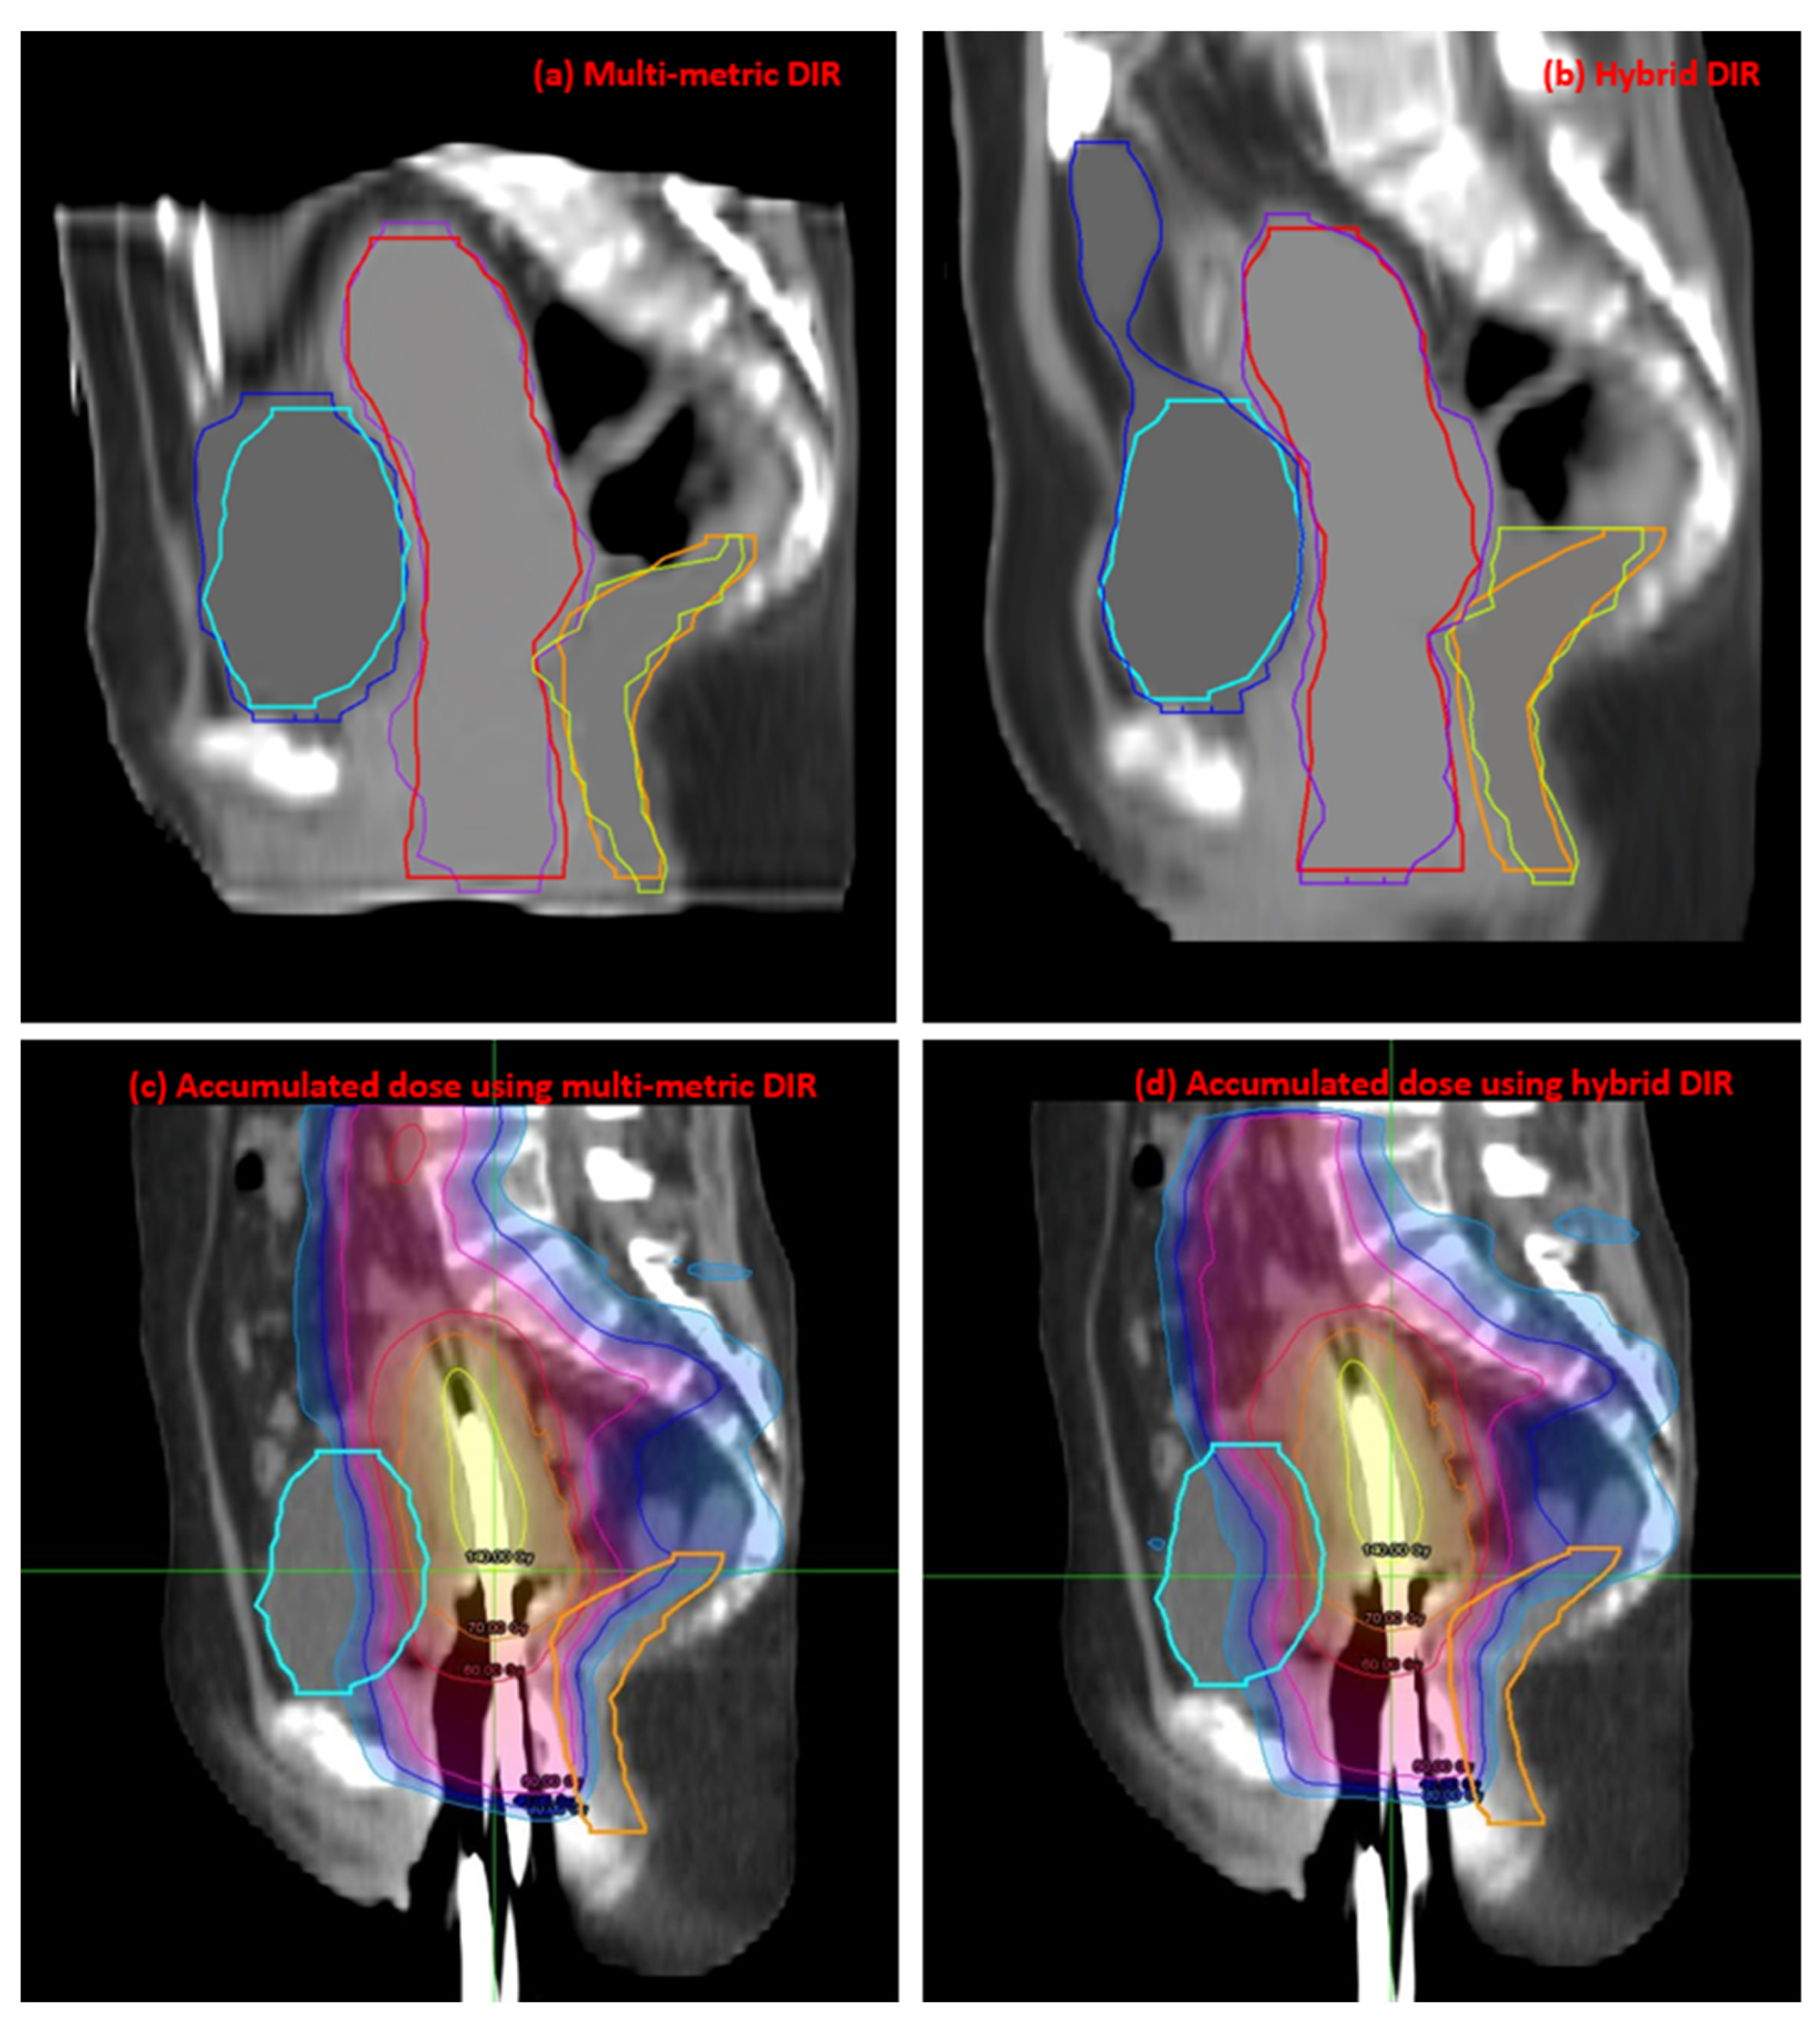

| Contour | Parameters | Multi-Metric | Hybrid | p-Value |

|---|---|---|---|---|

| Bladder | DSC | 0.84 ± 0.09 | 0.76 ± 0.15 | 0.001 |

| HD (mm) | 18.68 ± 9.99 | 41.98 ± 28.27 | <0.001 | |

| Rectum | DSC | 0.84 ± 0.04 | 0.77 ± 0.07 | <0.001 |

| HD (mm) | 14.23 ± 7.89 | 17.35 ± 10.01 | 0.155 | |

| U + V | DSC | 0.89 ± 0.02 | 0.86 ± 0.05 | 0.011 |

| HD (mm) | 16.92 ± 5.92 | 17.56 ± 9.85 | 0.756 |